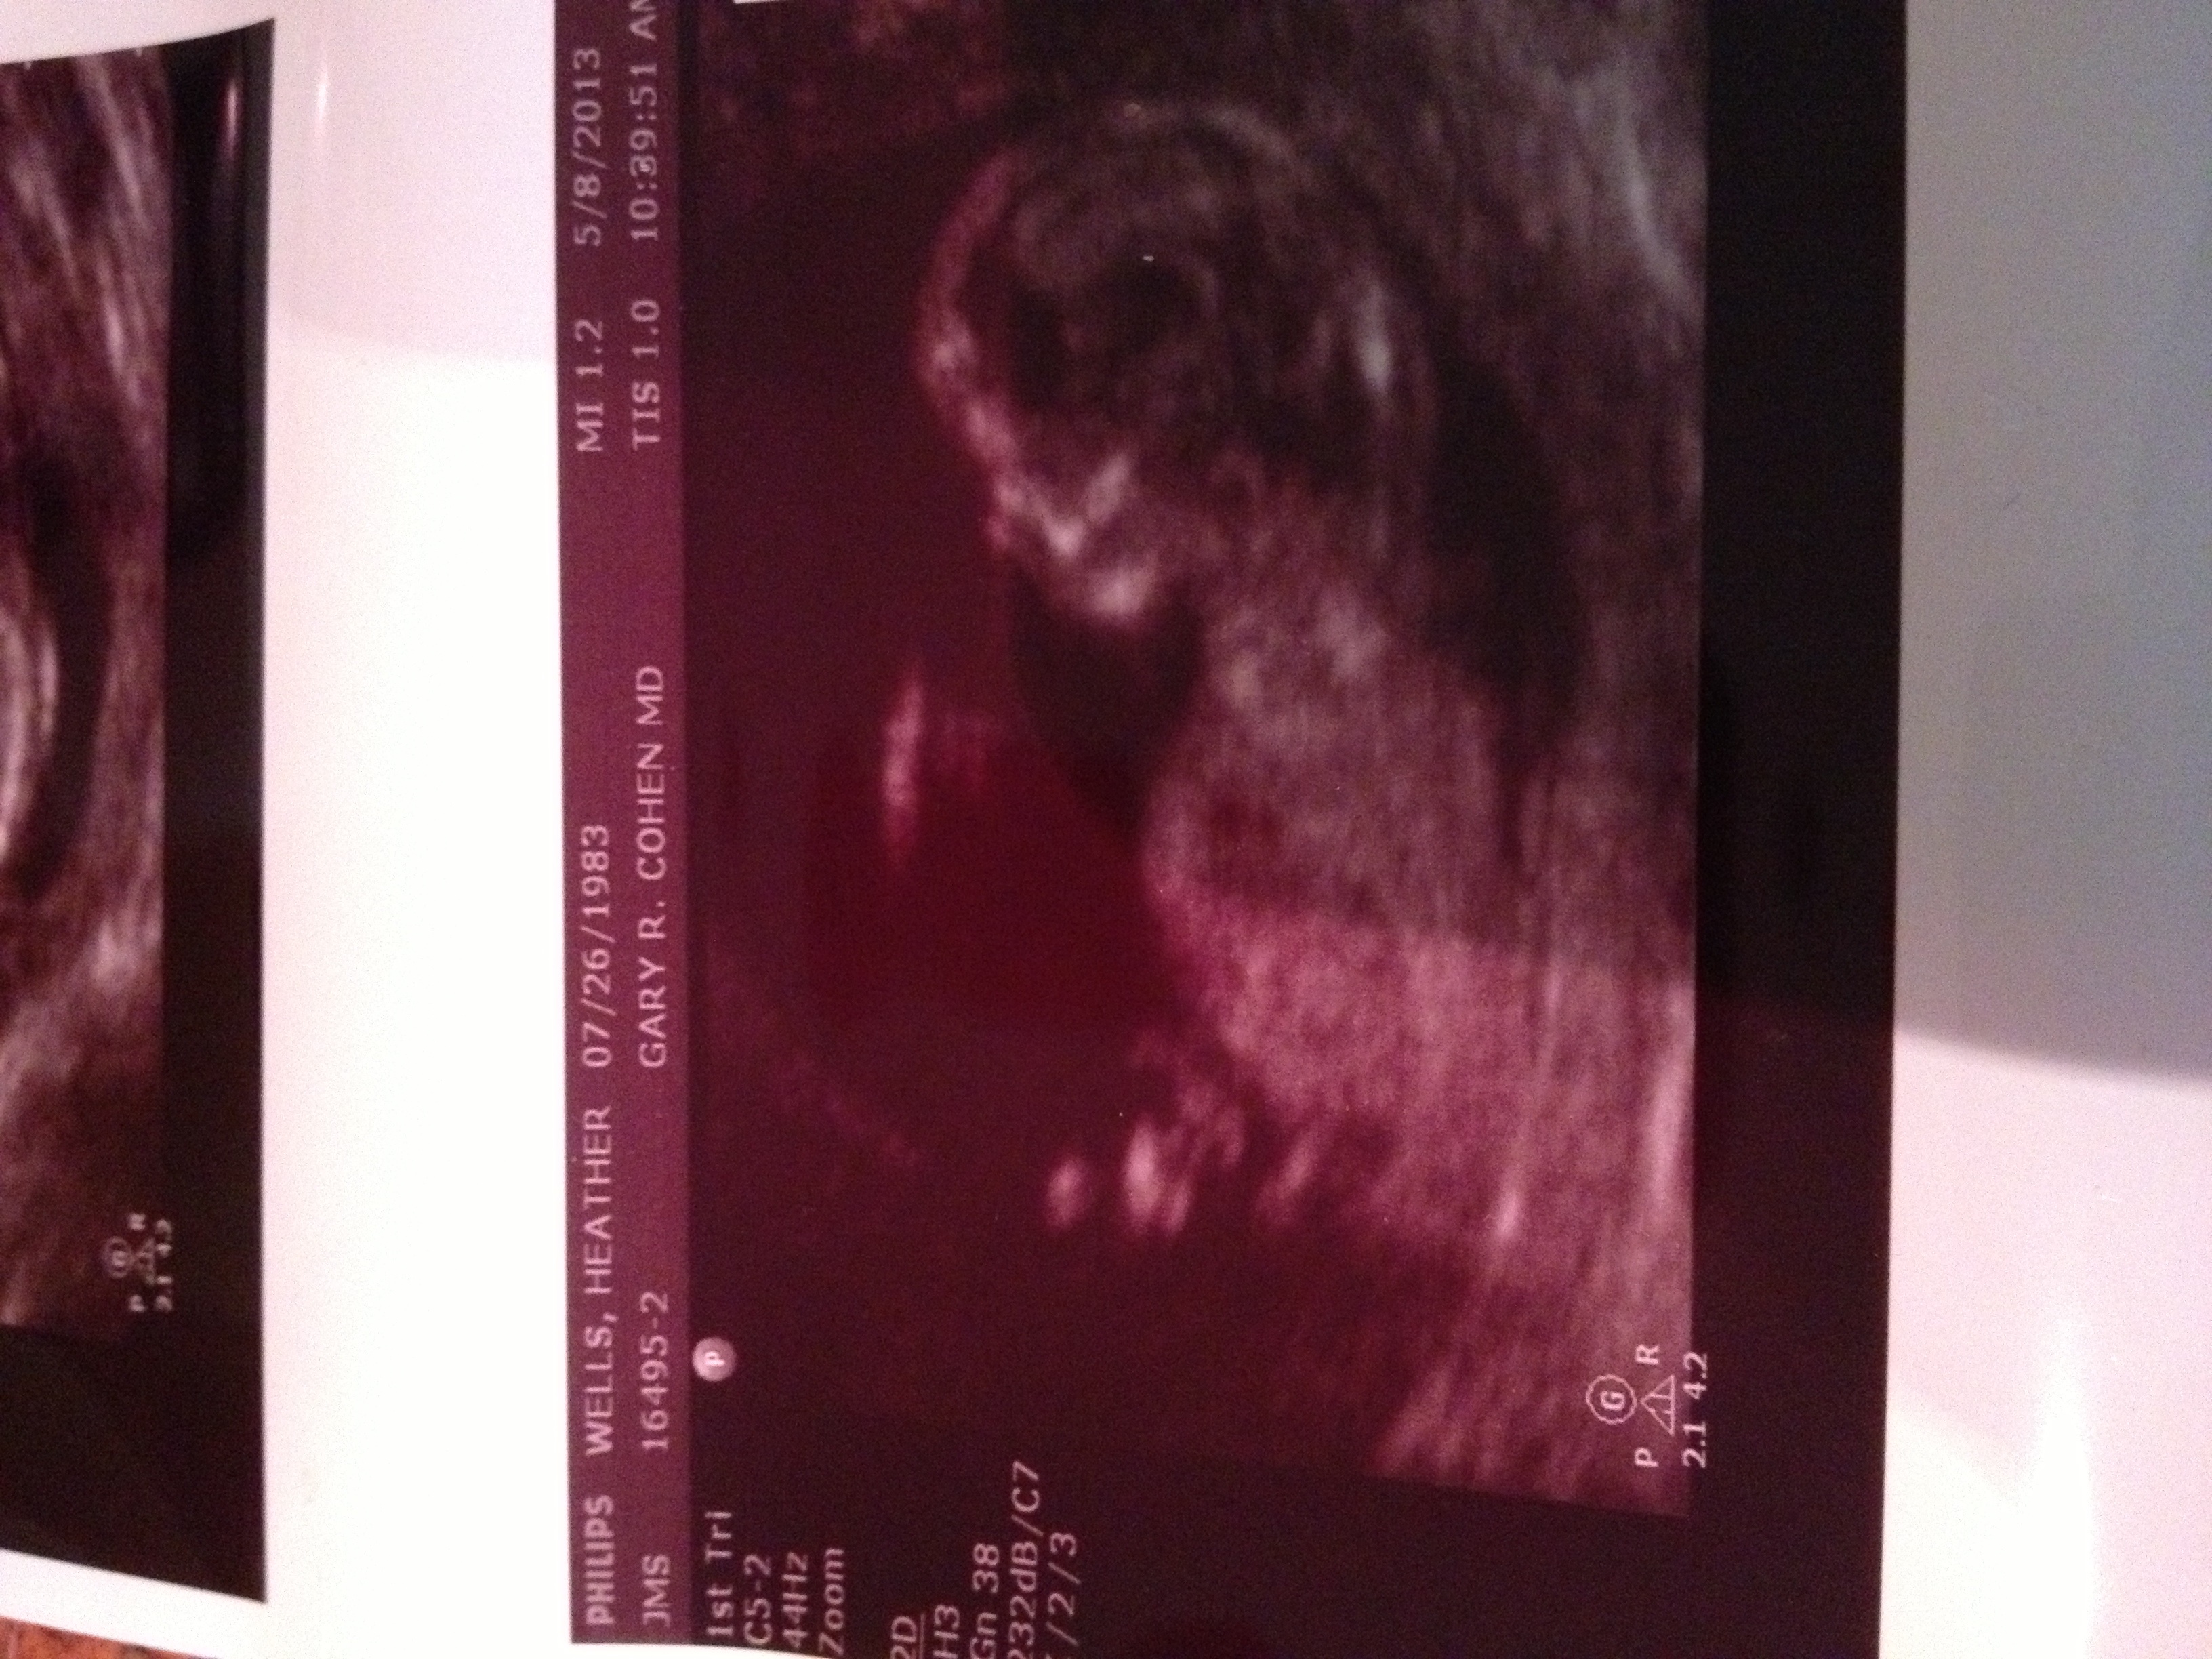

The first pic is a potty shot, the second shows the nub. I was either 12 w, 3 days or 13 w, 1 d. The experienced tech seemed confident it's a boy.

That's a boy the nubs pointing up